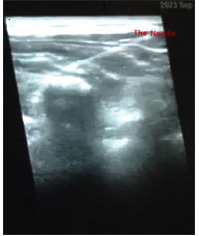

Methods: One hundred patients aged 4-12 years were randomly assigned into two groups, both groups received general anesthesia followed by bilateral sham erector spinae plane block at the level of T6 transverse process using 0.4 ml/kg normal saline on each side in the control group (group C) or bilateral ultrasound-guided erector spinae plane block at the level of T6 transverse process using 0.4 ml/kg ropivacaine 0.2% with a maximum dose of 2 mg/kg mixed with adrenaline 2 mcg/ml in erector spinae plane block group (group E). The postoperative pain scores were evaluated immediately post-extubation, at 1 hour, 2, 4, 6, 8, 10, 12, 14, 16, 18, 20, 22, and 24 hours after extubation, total consumption of intraoperative fentanyl and time to first rescue analgesic administration were also recorded.